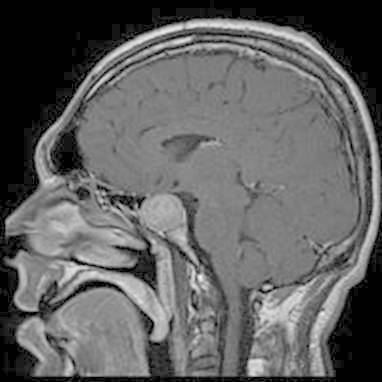

The cause of Alzheimer disease is unknown. Scientists know that in Alzheimer disease there is large build-up of proteins called amyloid within brain cells. These proteins occur normally, but not yet understand why they build up in large amounts. The disease process can go on for many years without symptoms, but as more and more proteins form brain cells,the cells lose their ability to function and eventually die. This causes the affected parts of the brain to shrink.